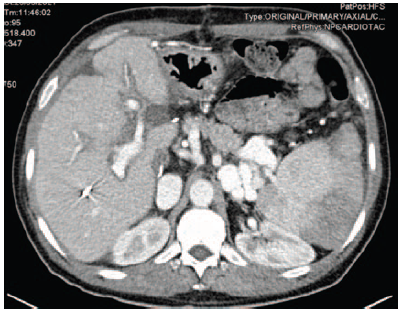

After she was hemodynamically stabilized, a total body computed tomography (CT) scan was performed. The CT scan excluded cerebrovascular events but showed a severe abdominal bleeding due to major liver trauma after mechanical cardiopulmonary resuscitation.

After an unsuccessful liver packing procedure, hepatic arteriography and subsequent superselective embolization of the VII segment arterial branches were performed, stopping the bleeding (Figure 1).

Figure 1. Computed Tomography Scan Results